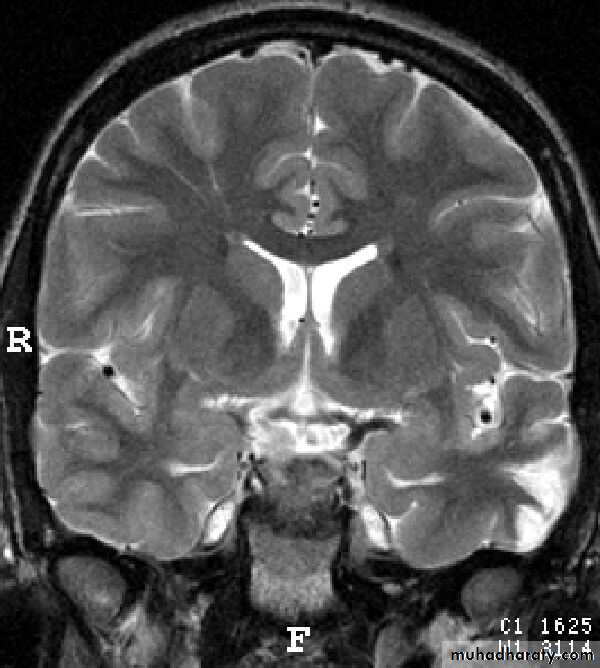

Common CT findings of traumatic brain injury